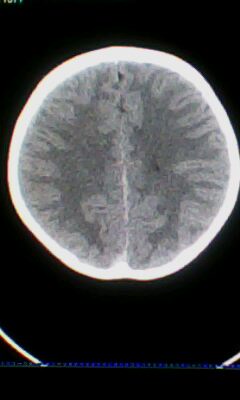

标题: PED3324:男 10岁 右侧 眼不自主抽动 自感颈部不适 [打印本页]

标题: PED3324:男 10岁 右侧 眼不自主抽动 自感颈部不适

蛛网膜下腔出血。

蛛网膜下腔出血可能。

颅脑ct轴位平扫颅内未见明确异常;建议必要时行mri检查。

窗调的不好,图像感觉怪怪的,不好说有什么明显异常,可建议mri检查。

颅脑ct轴位平扫颅内未见明确异常。